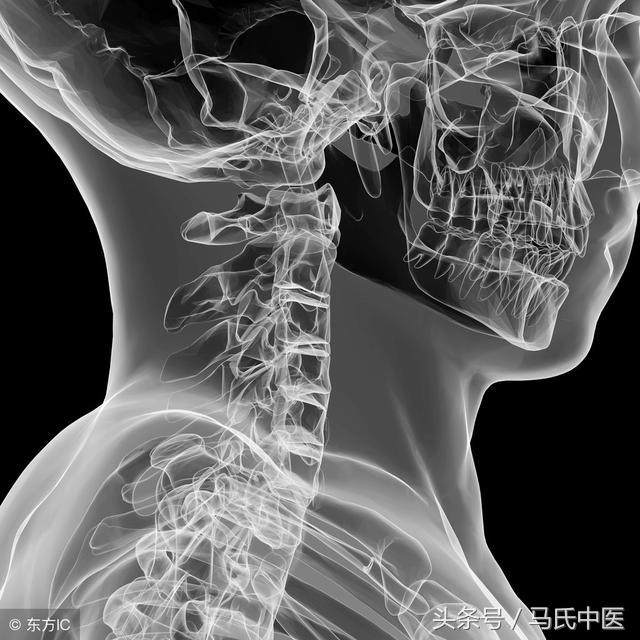

Jul 22, 19 · 福州看颈椎压迫神经引起手麻哪家好?手机、电脑的普遍应用,产生了一个新名词:低头族。颈椎是承载人体头颅重量并连接躯干与头颅的重要位置,主要由颈椎骨质结构等构成,内有传达大脑对肢体指令的脊髓和神经走行。颈椎病对人体的造成的主要危害便是压迫脊髓或(和)神经。Sep 01, 15 · 颈椎压迫神经引起手麻怎么办 临床上对于神经压迫造成的手麻往往采用保守治疗的方法。 常见的保守治疗方法主要包括药物缓解、推拿按摩、牵引治疗、针灸疗法、理疗法等。 药物缓解:一般急性期选择一些常用神经抑制类药物、镇静剂、维生素之类的药物,对患者的症状有一定的缓解功效;如果手麻病史较长较为严重可以使用安颈贴之类的药物治疗,多是由活血化瘀Oct 14, 13 · 手麻便是神经根型颈椎病的症状之一,当人步入中年之后,随着年龄的增长,一些器官往往会发生退行性变,当颈椎间盘发生退行性变后,往往会导致颈椎间盘突出或颈椎关节增生和肥大,这些突出的颈椎间盘或增生的关节一旦压迫临近的颈神经根时,便会引发

颈椎压迫神经 典型症状 每日头条

坐的时间长了会手麻 头晕 脖子疼 是颈部神经压迫所致 上游新闻 汇聚向上的力量